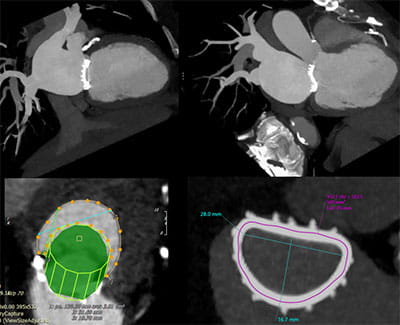

• High volume program with daily case averages of 10 CMR studies and 25-35 cardiac CTAs (50% coronary CTA, 30% structural, 20% other). Broad case complexity, including CAD, structural heart pathologies, congenital heart disease,  and implantable devices. Routine use of cutting edge technology, including T1/ECV mapping, quantitative perfusion, free-breathing CMR exam, artificial intelligence based CT analyses, CT-FFR, structural planning and simulation.